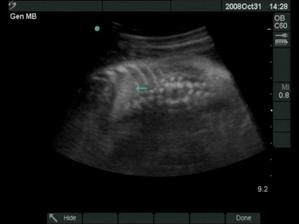

18.12.2008 prišli na svet o 3 týždne skôr naše krásne dvojičky. Ako prvá predrala cestu svojmu bratčekovi Laura, ktorá išla hlavičkou. Prišla na svet 12:53 a vážila 2720 g a merala 46 cm. Marko mal výjsť hneď na to zadočkom, ale keď zistil že sa mu uvoľnilo miesto asi si to rozmyslel a rozhodol sa v brušku zostať a spriečil sa. Pán doktor ho musel síce trochu povykrúcať aby ho dostal von, ale našťastie sa mu to podarilo a nemuseli maminu po normálnom pôrode aj rezať 🙂 Svetlo sveta uzrel Marko 13:03 a vážil 2890 g a meral 48 cm.